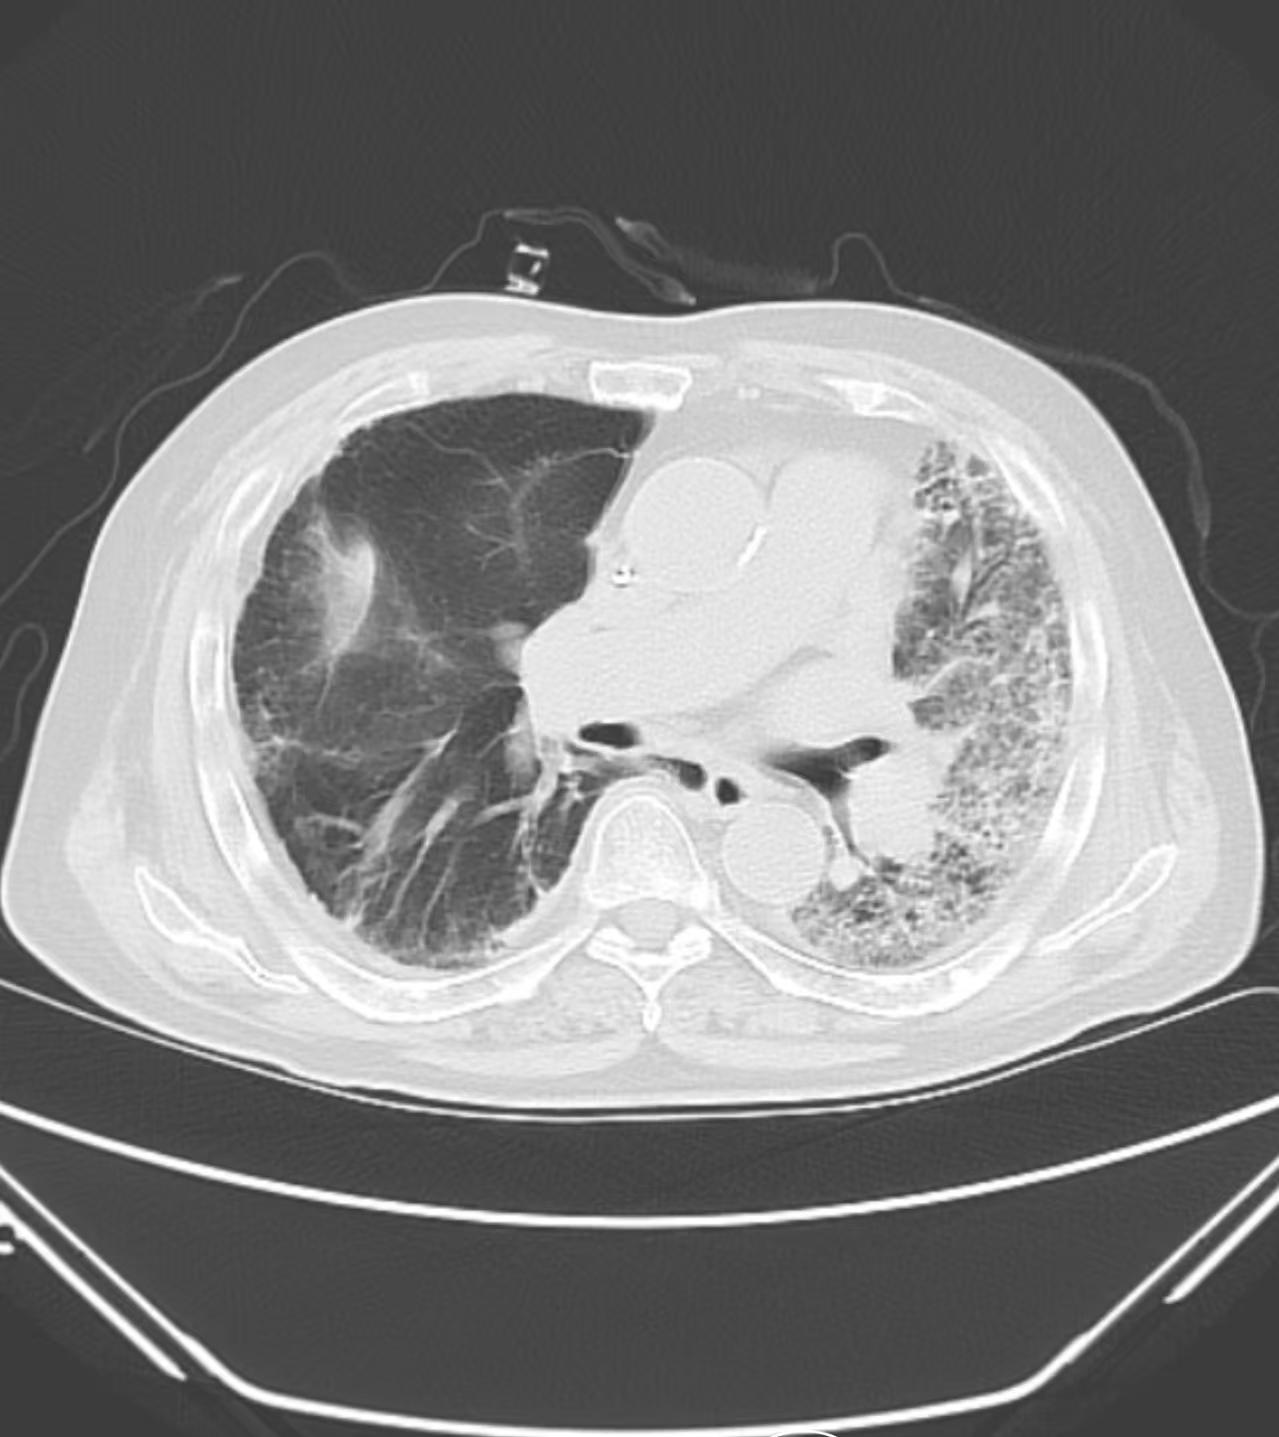

普通人最怕的是肺癌,但我告诉大家比肺癌更可怕的病有很多种,今天讲一种肺部疾病,其发展速度之快,普通人难以想象,而这种疾病可能90%的人都没有听说过,这个就是间质性肺病。 这其中分几种情况,第1种就是大家耳熟能详的病毒性肺炎,它虽然是一种肺炎,但跟普通的肺炎不同,它呈现出弥漫性的间质性改变,这种情况短时间内可能会引起呼吸衰竭,炎症风暴导致的炎症难以抑制,迅速威胁生命,甚至所有的好药用上都拉不回来。 还有一类间质性肺病的患者,从没有疾病到最终去世,甚至只要短短的一个月时间,这种疾病叫做无肌炎性皮肌炎导致的间质性肺病,其中尤以抗mda5抗体阳性的患者,发病最为快速,我曾经遇到一个用三无焗油膏焗油的农村女性,发病前甚至还在下地干活,焗油之后,迅速出现头部及背部的皮疹,很快肺纤维化,三周左右就因呼吸衰竭去世。 还有就是百草枯导致的间质性肺病,这个大家在新闻上都有看到过,百草枯导致的农药中毒,除了导致肝肾衰竭之外,最严重的是肺纤维化,死亡率极高。 除了这些,你还见过哪些肺部疾病威胁生命的情况?大家可以在评论区讨论,以供相互借鉴,积极预防。